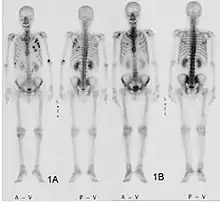

La scintigraphie osseuse est actuellement encore le meilleur moyen de diagnostic des métastases osseuses. Ce procédé est relativement sophistiqué, coûteux et soumis à quelques limites diagnostiques[90]. Contrairement à la radio, on peut avec la scintigraphie représenter assez simplement l'ensemble des attaques du squelette[87]. Une scintigraphie osseuse est normalement bien plus sensible pour la détection des métastases osseuses qu'une radio. La sensibilité de la scintigraphie osseuse est assez élevée, avec 95 %. En moyenne, avec cette méthode, les métastases osseuses sont détectées six mois avant leur mise en évidence sur la radio[113]. Par contre la spécificité est substantiellement plus faible[114], car presque toutes les modifications tumorales ou inflammatoires du squelette conduisent à un enrichissement en radiotraceurs dans le voisinage. Le remodelage plus élevé et les processus de réparation dans la bordure des métastases osseuses ostéolytiques conduisent à une accumulation plus élevée du radiotraceur, visible comme un « point chaud » sur l'image de scintigraphie[115]. Un phénomène observable de rebond (flare up) peut être dû à l’augmentation de l’activité ostéoblastique au niveau des zones d’ostéolyse tumorale clinique, dont la colonisation métastatique a été éradiquée par le traitement ; il ne doit pas être confondu avec une progression métastatique, au risque de modifier le traitement de façon intempestive[116]. Dans les métastases osseuses de cancer du poumon ou du sein, la néoformation réactive d'os peut dans de rares cas être absente[117]. Sur la scintigraphie, ceci apparaît alors comme un « point froid », un domaine avec une absorption réduite du radiotraceur[118].

Pour le myélome multiple purement ostéolytique, on ne reconnaît sur la scintigraphie osseuse aucun changement[87]. Alors que sur la radio, le résultat de la sommation de tous les processus d'échange de matière dans l'os se voient sur une longue période, la scintigrapie osseuse présente un instantané des processus d'échange de matière en cours dans l'os. C'est pourquoi les métastases osseuses ostéocondensantes, qui se déroulent avec un taux d'échange de matière très bas, restent imperceptibles à la scintigraphie[119].

La scintigraphie osseuse est avant tout utilisée pour le contrôle de la thérapie, que ce soit une chimiothérapie, une radiothérapie externe ou métabolique, pour la détermination des stades, notamment pour les cancers avec tumeur primitive inconnue, et pour le suivi après cancer[87].